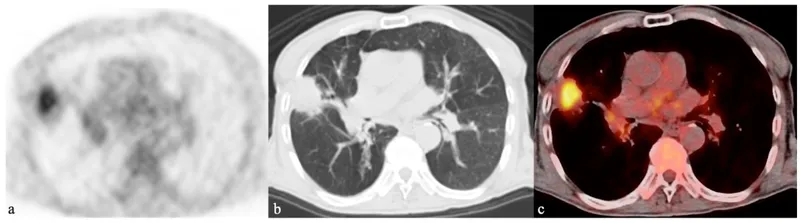

$^{18}$F-FDG PET/CT (Fluorodeoxyglucose):

- Mechanism: Glucose analog; accumulates in cells with high glucose metabolism (malignancy, inflammation, infection).

- Key Pulmonary Uses:

- Oncology: NSCLC staging (nodal/distant mets), SPN characterization (SUVmax >2.5 suggests malignancy), therapy response, recurrence detection.

⭐ FDG PET/CT is superior for NSCLC staging and crucial for characterizing indeterminate SPNs.

- 18F-FDG PET-CT: Essential for lung cancer staging & SPN (Solitary Pulmonary Nodule) assessment.